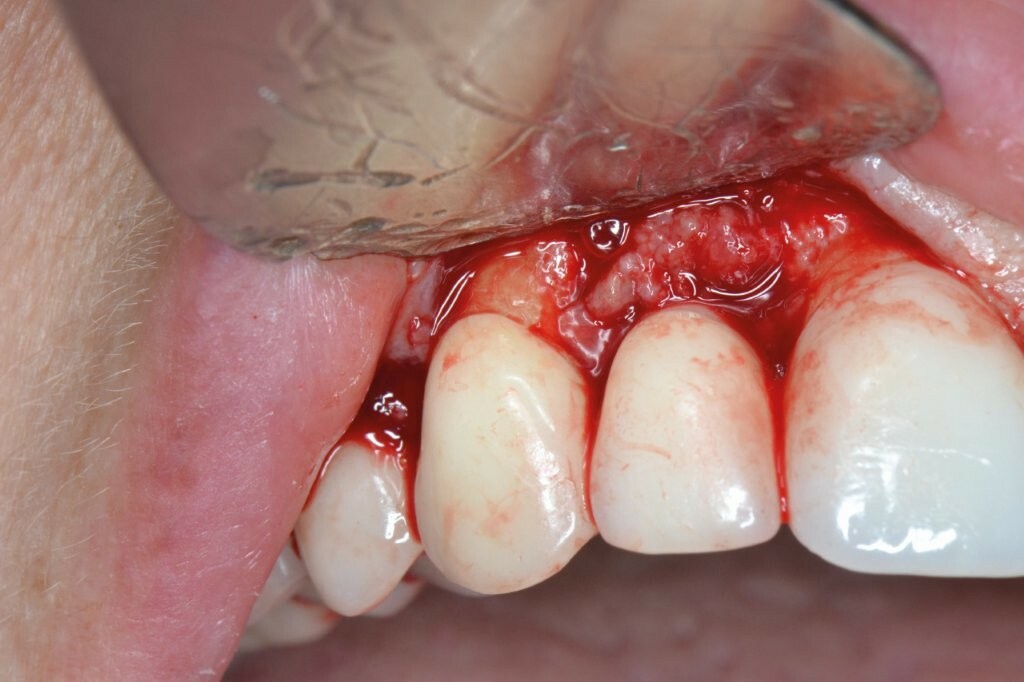

Wir beschlossen, den Fall chirurgisch anzugehen, um die Infektion zu beseitigen und den periimplantären Defekt zu behandeln.

Ein Minilappen wurde sowohl bukkal als auch palatinal am Implantat unter Einbeziehung der beiden Nachbarzähne gebildet. Das entzündete Gewebe wurde kürettiert, wobei wir einen 3 mm großen horizontalen Defekt mit einem stärkeren Knochenverlust auf der bukkalen Seite feststellten. Gemäß des zuvor beschriebenen Protokolls erfolgten zwei aufeinanderfolgende 5-minütige Anwendungen von OXYSAFE-Gel. Der Defekt wurde vorsichtig mit einem Xenotransplantat aufgefüllt und mit einem Kollagenvlies abgedeckt, der Lappen anschließend koronal mit einer Kopfnaht vernäht.